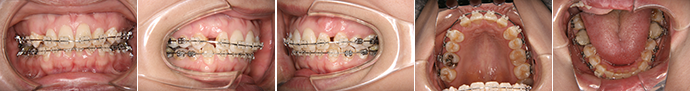

| 主訴 | 前歯の隙間が気になる |

| 年齢・性別 | 42歳 / 女性 |

| 治療方針 | 咬合力により上顎前歯が前方に傾斜したと思われるケース。元に戻りやすいため過蓋咬合をしっかり治して、保定には固定式のリテーナーも併用する。 |

| 抜歯部位 | 非抜歯 |

| 使用装置 | マルチブラケット装置 |

| 治療期間 | 16か月 |

| リテーナー | 上顎インビジブル、フィックス、下顎インビジブル |

| 費用 | 765,000円(税別) |